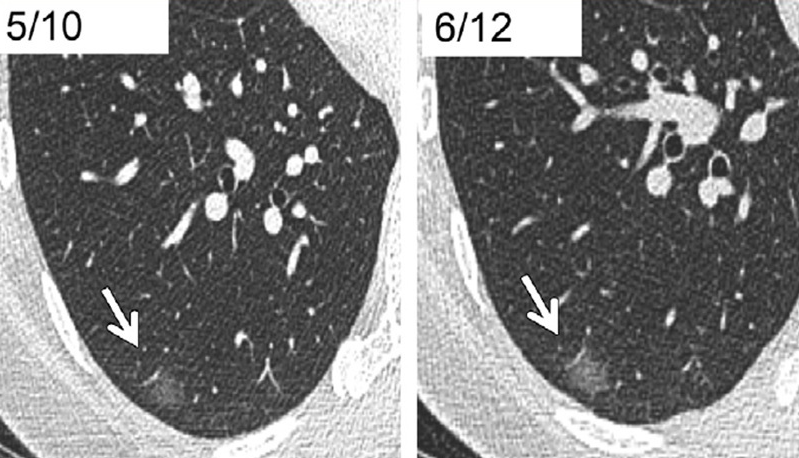

2、看结节大小:良性结节多是直径<5mm的微小结节

5、看增强ct:良性结节没有明显的强化 , 良性的可能性就比较大